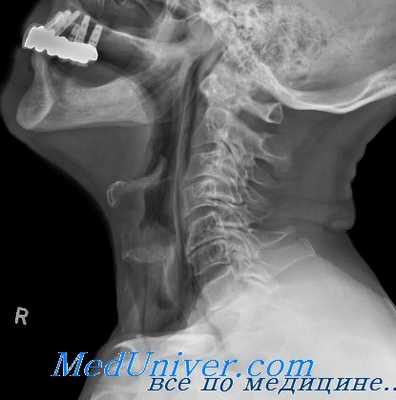

Верхнюю границу ротоглотки во время разговорной речи, пения, а также глотания, образует замыкающее глоточное кольцо. Средний отдел глотки ничем не отделен от нижнего отдела глотки и непосредственно в него переходит.

Нижний отдел глотки простирается до нижнего края перстневидного хряща. Во время голосообразования, когда надгортанник приподнят и вход в гортань широко отркыт, нижний и средний отделы глотки объединяются с преддверием гортани и создают общую резонаторную полость.

Средний и нижний отделы глотки составляют единую резонаторную камеру, ограниченную сверху замыкающим глоточным кольцом, спереди- языком, сзади — мышцами задней стенки глотки.

Верхний отдел глотки и носовая полость являются непосредственно сообщающимися между собой резонаторными камерами, однако, каждая из них имеет свое значение. Верхний отдел глотки может изменять свой объём благодаря сокращению мышц замыкающего глоточного кольца. Носовая полость — камера, ограниченная твёрдыми, неподвижными стенками; она может иметь значение резонатора только в том случае, если се основной тон гармонирует с составными тонами голоса.